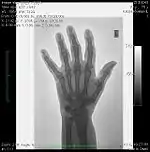

The maximum spatial resolution of an imaging system can be readily obtained by imaging a resolution test object - an example of which is shown in Figure 6.5, panel (a). The test object consists of narrow parallel slits in a lead sheet at spacings which decrease to beyond the maximum resolution of the image receptor. The minimum spacing resolved in images is called the Limiting Spatial Resolution and can be determined to be about 3.5 line pairs/mm from the figure.